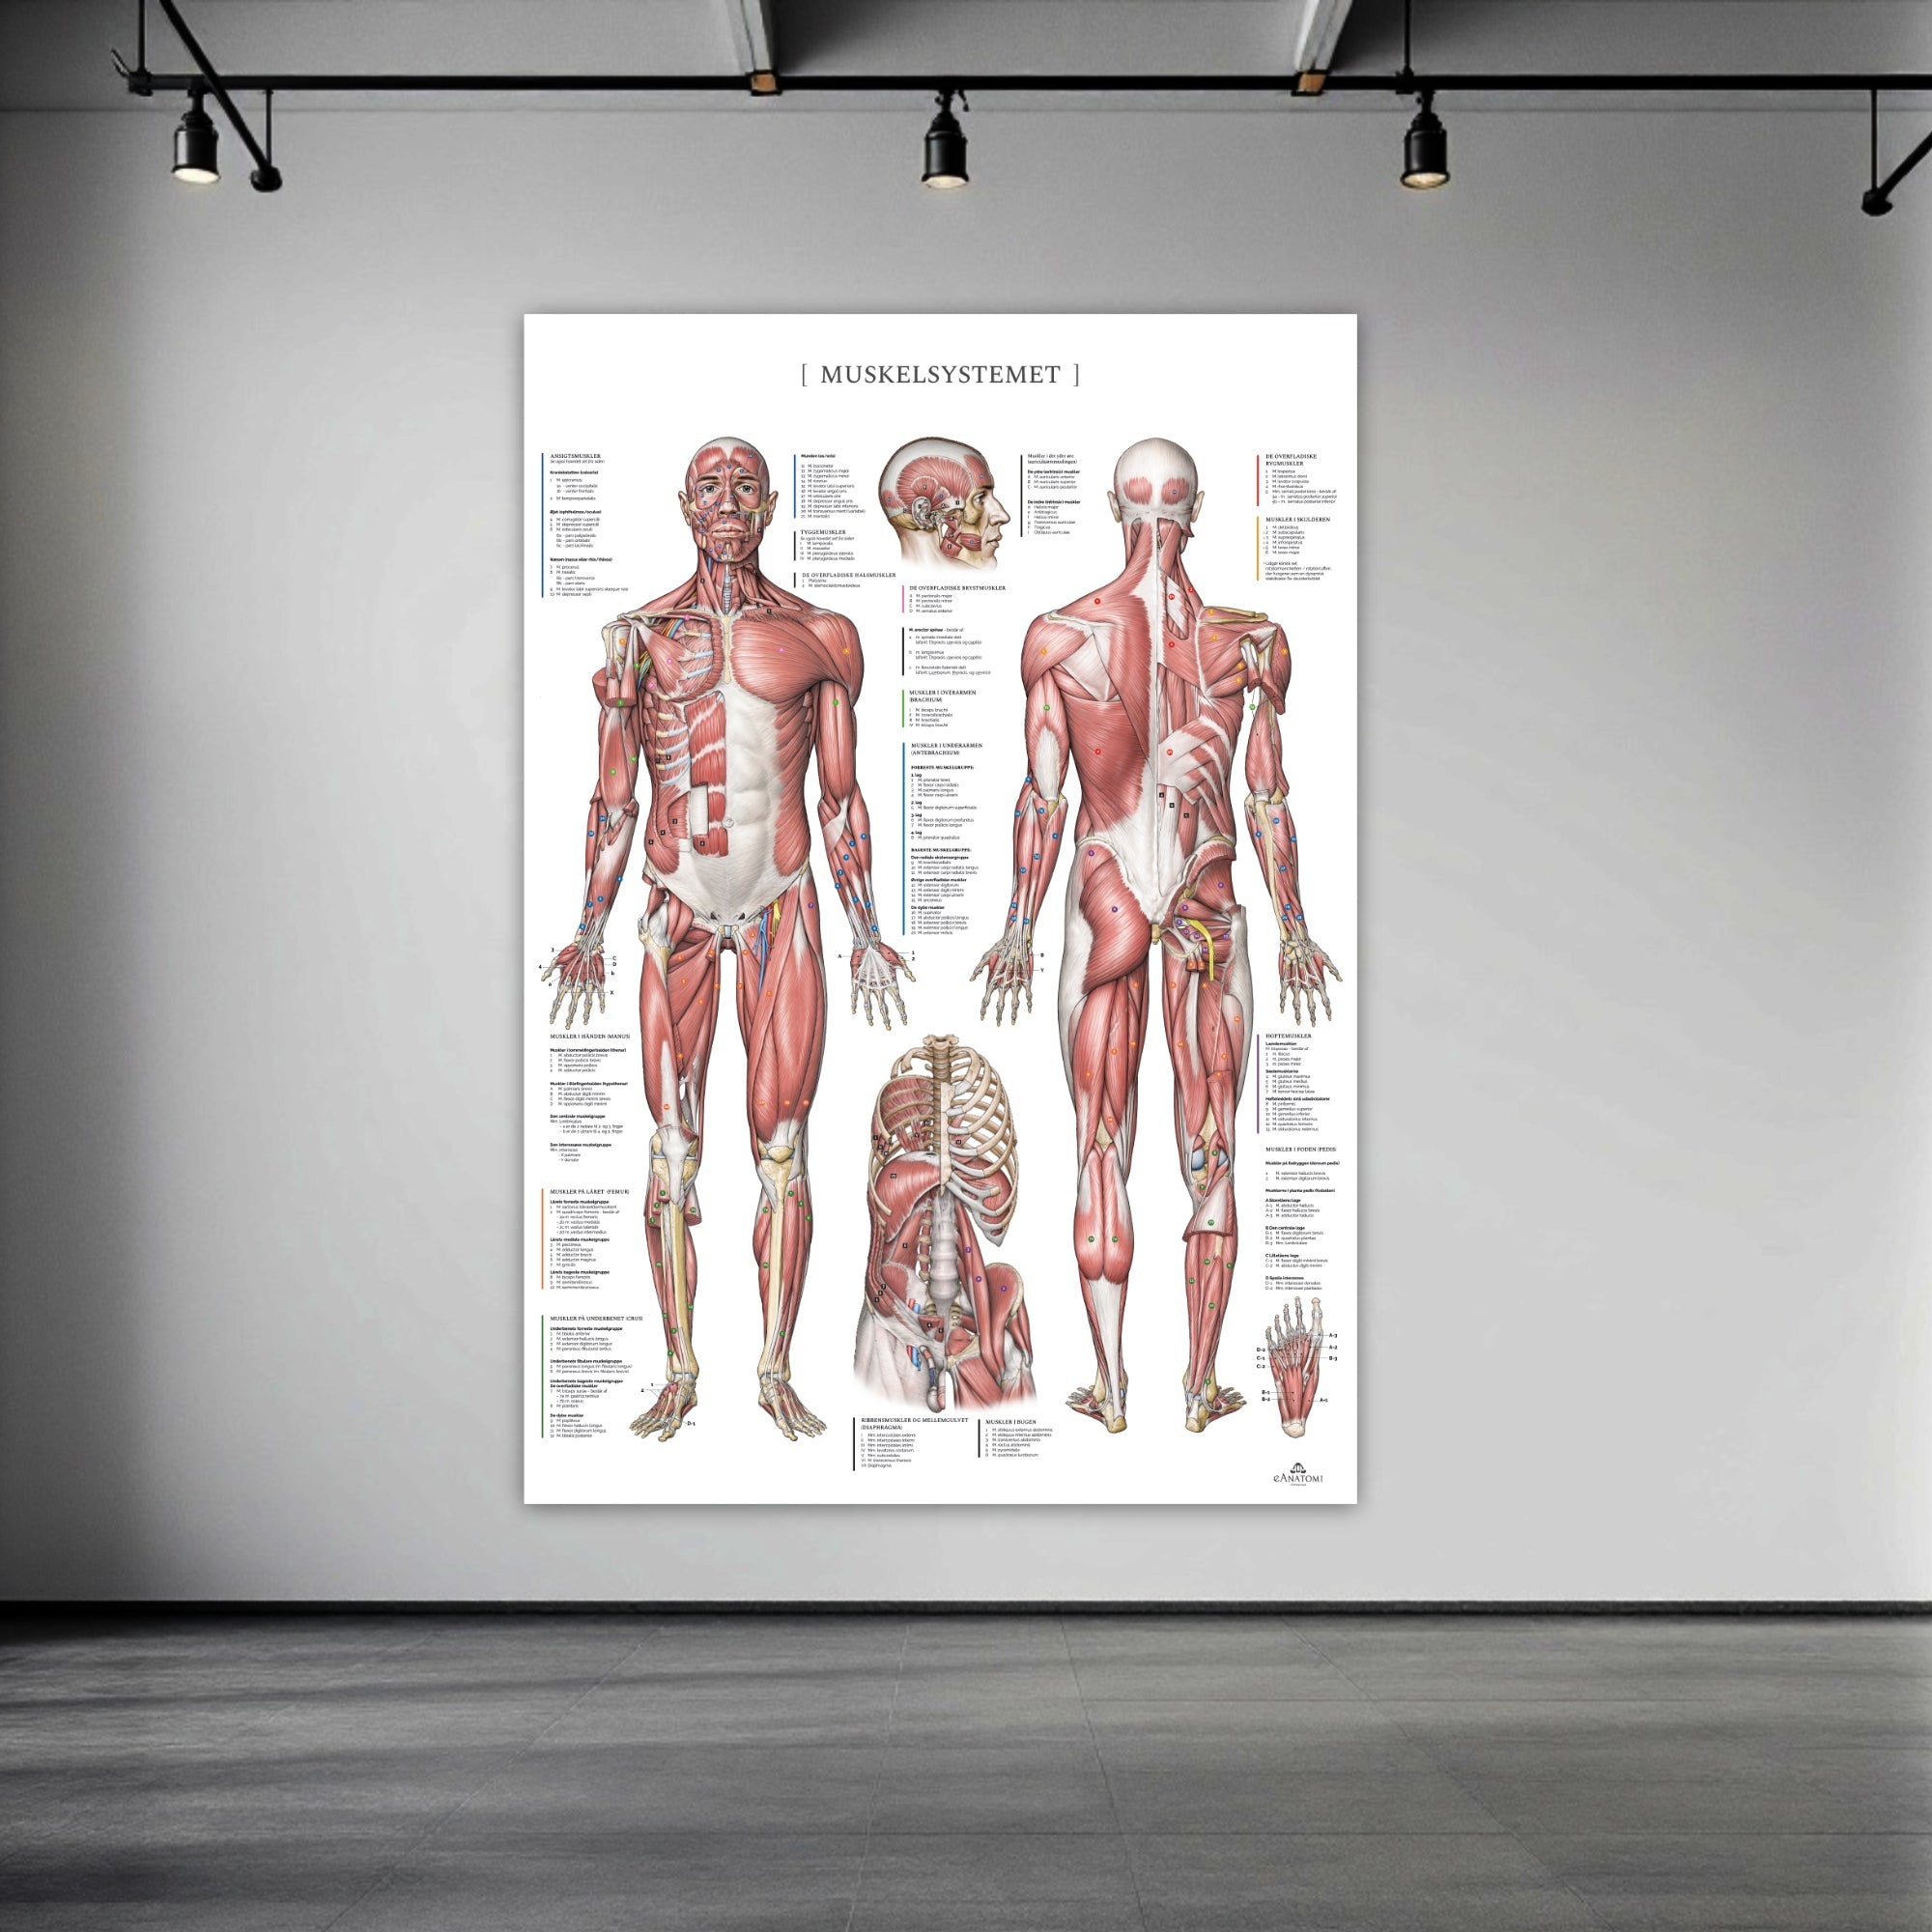

Andra produkter utvalda speciellt för dig

Vårt anatomiska produktsortiment